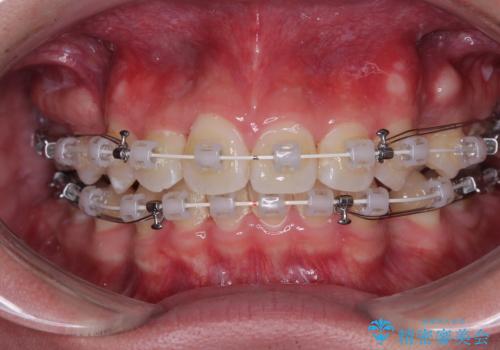

- 矯正装置

- 審美装置

- 今回ご紹介するのは、

「全体的なデコボコ(叢生)」「上下の正中のずれ」 を主訴として来院された20代男性の患者様の症例です。

叢生が強く、歯が並ぶスペースが不足していたため、

上下左右の第一小臼歯を抜歯して、矯正治療のための適切なスペースを確保する計画としました。